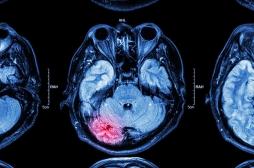

cancer du cerveau